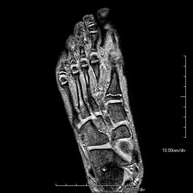

Exploració per estudiar aquesta articulació i les lesions freqüents de lligaments (esquinços), així com l'afectació d'altres estructures, com el cartílag o l'os. També és de gran utilitat per diagnosticar alteracions al tendó d'Aquil·les (tendinitis o trencaments). La durada aproximada és de 20 minuts. No utilitza radiació ionitzant. - RM de Peu

Exploració per a l'estudi de lesions en tendons, músculs i petites articulacions. Permet valorar amb eficàcia les lesions al cartílag. També és de molta utilitat per completar l'exploració ecogràfica prèvia. No empra radiació ionitzant. Té una durada aproximada de 20 minuts. - Artro-RM d'Espatlla